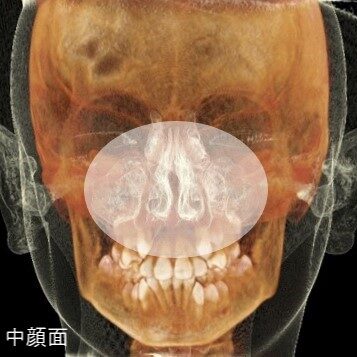

顔の中心、中顔面といわれる領域は、本来上前方へと成長するのが健全な形です。

そのガイド役を担っているのが「上顎についている舌」です。また、この舌は唇や頬からの力とのバランスをとり、歯並びの形成においても大切な役割があります。

鼻呼吸がきちんとできていると、中顔面や歯並びが健全な成長をしやすくなります。